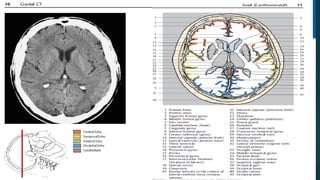

Este documento es el programa para un taller de imágenes del curso de emergencia 2015 impartido por el Dr. Víctor Delgado. El taller se centra en el uso de imágenes médicas para el diagnóstico y tratamiento de pacientes en coma traumático según la base de datos de Marshall. El Dr. Delgado es el único instructor repetido a lo largo del documento.